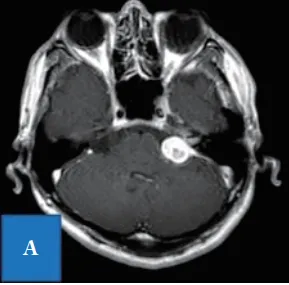

本例为51岁男性患者,一年前确诊听神经瘤。虽未出现面神经麻痹症状,但左耳听力严重受损至105dB,生活陷入半静默状态。MRI检查显示肿瘤直径达24mm,并已侵入内耳道。

入院时T1加权磁共振成像显示,延伸至内耳道的桥脑角区存在均匀强化病灶。